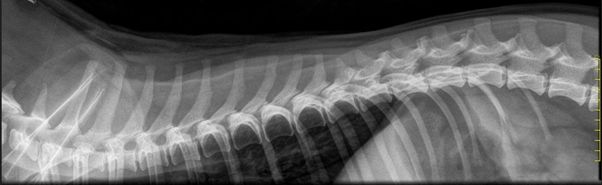

”Kyynärnivelen epäyhdenmukaisuus näkyy parhaiten röntgenkuvassa, jossa niveltä ei ole taivutettu (avautumiskulma

90 astetta tai enemmän). Röntgenkuvassa täytyy näkyä kyynärnivelen lisäksi koko kyynärvarsi.” (Anu Lappalainen/ Kennelliitto)

Kuvantamisesta käytetään yleisesti lyhennettä INC.

Havannankoira voi saada virallisen INC-lausunnon täytettyään 12 kuukautta. Tutkimus tehdään rauhoituksessa röntgenkuvauksella. Eläinlääkäriasema lähettää kuvat Kennelliittoon lausuttavaksi. Koiran omistajan on tehtävä lähete Kennelliiton Omakoira-palvelussa ennen tutkimusta, että tulos saadaan virallisesti lausuttuna ja tulos tallennetaan jalostustietojärjestelmään.